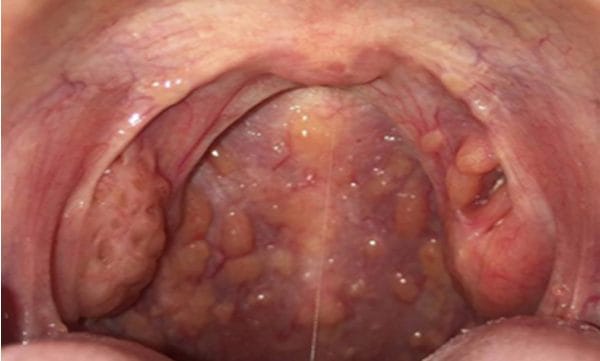

3. Viêm họng hạt

Viêm họng hạt là một dạng tiêu biểu của viêm họng mãn tính, đặc trưng bởi tình trạng viêm nhiễm kéo dài liên tục khiến niêm mạc bị sung huyết và xuất tiết liên tục từ đó hình thành các hạt màu đỏ hoặc hồng ở thành sau họng. Bệnh phát triển ở những người bị viêm họng tái phát nhiều lần, dai dẳng.

Nguyên nhân hình thành các hạt này là do cơ thể bị nhiễm trùng trong thời gian dài khiến cho các nang lympho - có vai trò bảo vệ cơ thể và các cơ quan hô hấp khỏi virus, vi khuẩn - phải hoạt động quá mức từ đó dẫn đến tình trạng tăng sản, hình thành các hạt nổi cộm phía trong niêm mạc họng.

Các triệu chứng đặc trưng của viêm họng hạt bao gồm:

- Thành họng xuất hiện các hạt đỏ, hồng lồi cao hơn so với niêm mạc xung quanh.

- Luôn có cảm giác vướng víu, ngứa và khô họng, đặc biệt sau khi ngủ dậy.

- Có cảm giác đau khi nuốt thức ăn, uống nước hoặc thậm chí là nuốt nước bọt.

- Bệnh nhân thường phải đằng hắng hoặc cố gắng khạc đờm, đờm đặc quánh, màu trắng đục.

- Cổ nổi hạch, sờ thấy cứng, đau khiến cho bệnh nhân sốt, đau đầu…